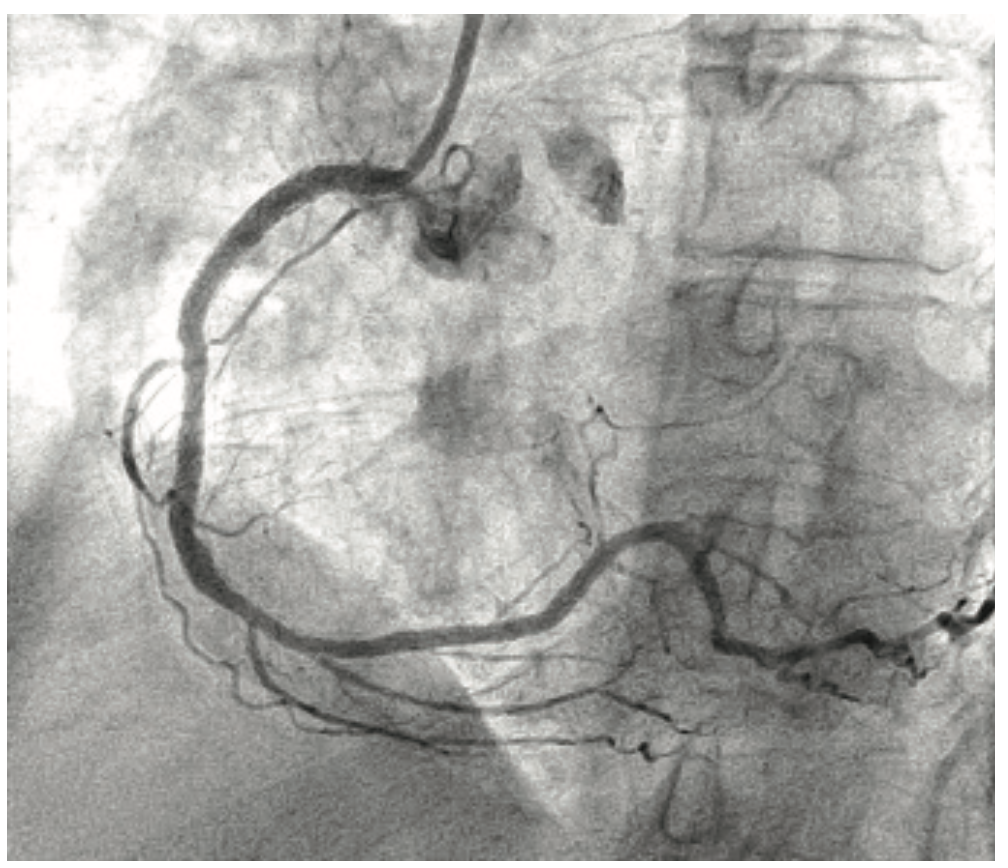

The patient’s prior procedures were performed via transfemoral approach and on one occasion, she experienced severe local pain due to vascular hemorrhage. The coronary brachytherapy procedure was performed using left radial artery access with a 6 Fr 10 cm long Slender Glidesheath (Terumo) and anticoagulation with bivalirudin. Baseline angiography showed sequential, high-grade restenotic lesions in the proximal right coronary artery (RCA) stents in addition to significant stenosis at the outflow of the most distal stent (Figure 2A). The in-stent restenosis was treated with laser atherectomy using an X-80 excimer catheter (Spectranetics) followed by balloon angioplasty with a 3.5 mm Angiosculpt scoring balloon (Spectranetics) and 4.0 mm NC Euphoria balloon (Medtronic). The most distal lesion, which extended beyond the prior stents, was treated with a new Promus DES. Coronary brachytherapy of the proximal lesions was then performed with a Beta-Cath 40 mm long source for a treatment dose of 23 Gray (Figure 2B). Final angiographic result is shown in Figure 2C. Repeat cardiac catherization at 3 months, performed because of chest pain, demonstrated widely patent stents. The patient has continued on aspirin and clopidogrel, and remains symptom-free 1 year post procedure.

An 87-year-old man with prior coronary artery bypass surgery in 1998 and history of diabetes, hyperlipidemia, hypertension, and prior smoking, underwent PCI with Resolute DES placement for disease at the distal anastomosis of a 16-year-old saphenous vein graft (SVG) to the left circumflex obtuse marginal branch. During the following two years, he experienced numerous episodes of acute coronary syndromes due to recurrent in-stent restenosis, requiring four additional PCI procedures and multiple additional DES (Figure 3). Within two months of his fifth PCI procedure, he developed recurrent prolonged angina with a non-ST segment elevation MI (peak troponin T 0.12 ng/ml). Echocardiography demonstrated significantly reduced global left ventricular function with an ejection fraction of 30%. He was referred to our institution for coronary brachytherapy.

Left radial access was obtained with placement of a 6 Fr 10 cm Slender Glidesheath. Heparin and eptifibatide were used for anticoagulation. A 6 Fr Amplatz left (AL) 1 short tip guiding catheter (Cardinal Health) was used to provide extra backup support. Angiography demonstrated a diffuse subtotal in-stent restenosis of the distal SVG (Figure 4A). Laser atherectomy was performed with an X-80 excimer laser, followed by balloon angioplasty with 3.0 mm Angiosculpt scoring balloon and 3.5 NC Trek balloon (Abbott Vascular). Coronary brachytherapy was then administered using a 40 mm Beta-Cath source train, with a dwell time of 4 minutes, 48 seconds to deliver a dose of 23 Gray. The final angiographic result is shown in Figure 4B. The patient continues to do well post procedure and remains on dual antiplatelet therapy.